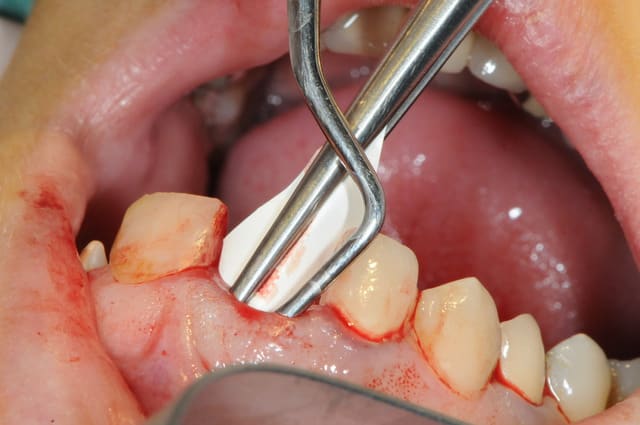

tu peux aussi faire ça;

glisser et interposer une membrane entre la parois vestibulaire osseuse et le périoste que tu décolles en partant de l'alvéole et en restant en contact osseux...